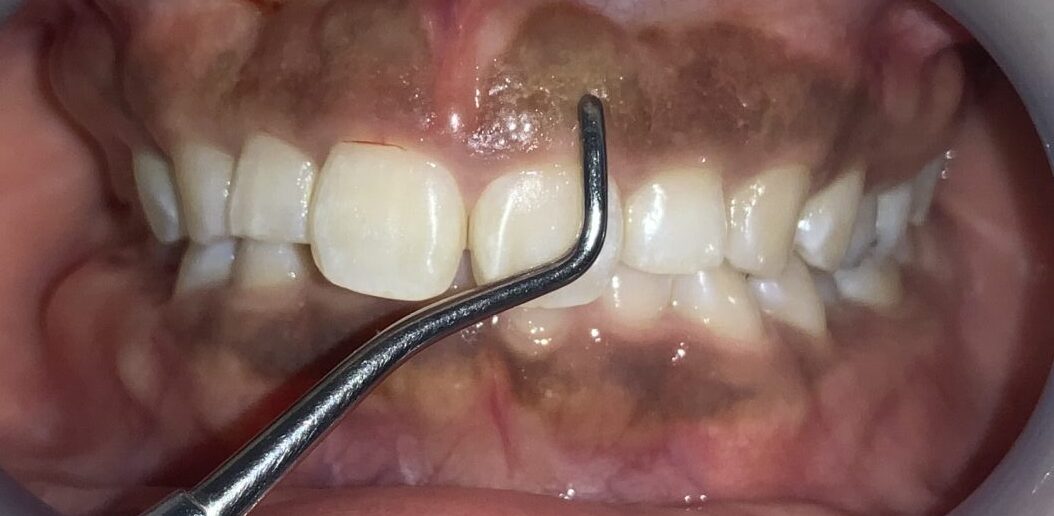

今回の患者様の治療前の状態です。

歯ぐきの長さに比較して、歯が少し小さいですね。歯ぐき自体は健康で綺麗なピンク色をしています。

一番気になる、前歯の歯と歯ぐきの位置状態の検査します。

こんなに歯ぐきがかぶさっています。